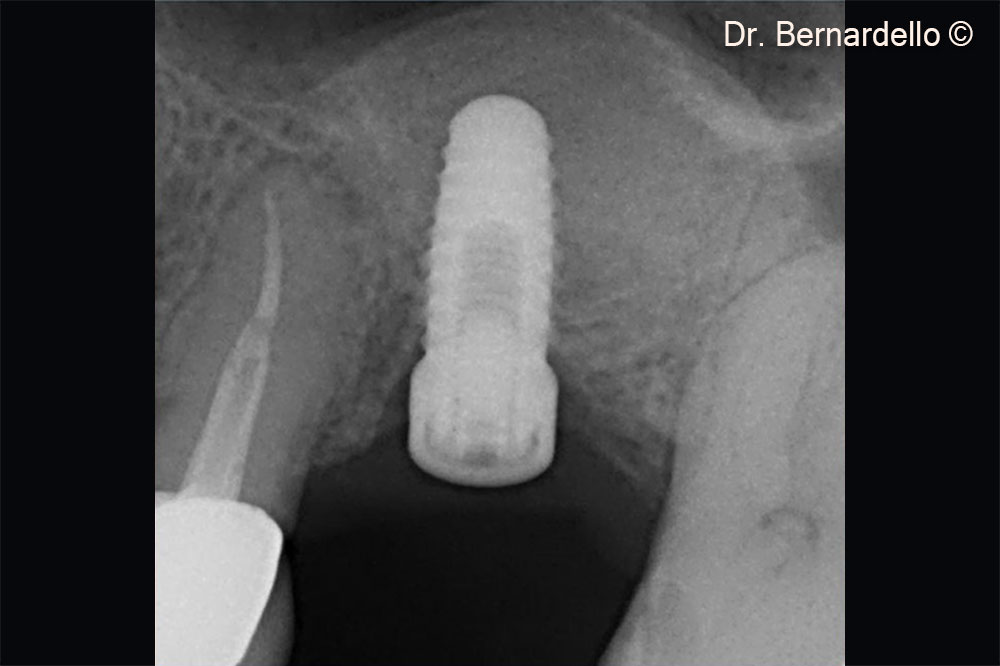

Dựa trên chiều rộng xoang, bệnh nhân nữ (55 tuổi) được coi là đủ điều kiện để thực hiện phẫu thuật nâng sàn xoang qua mào xương.